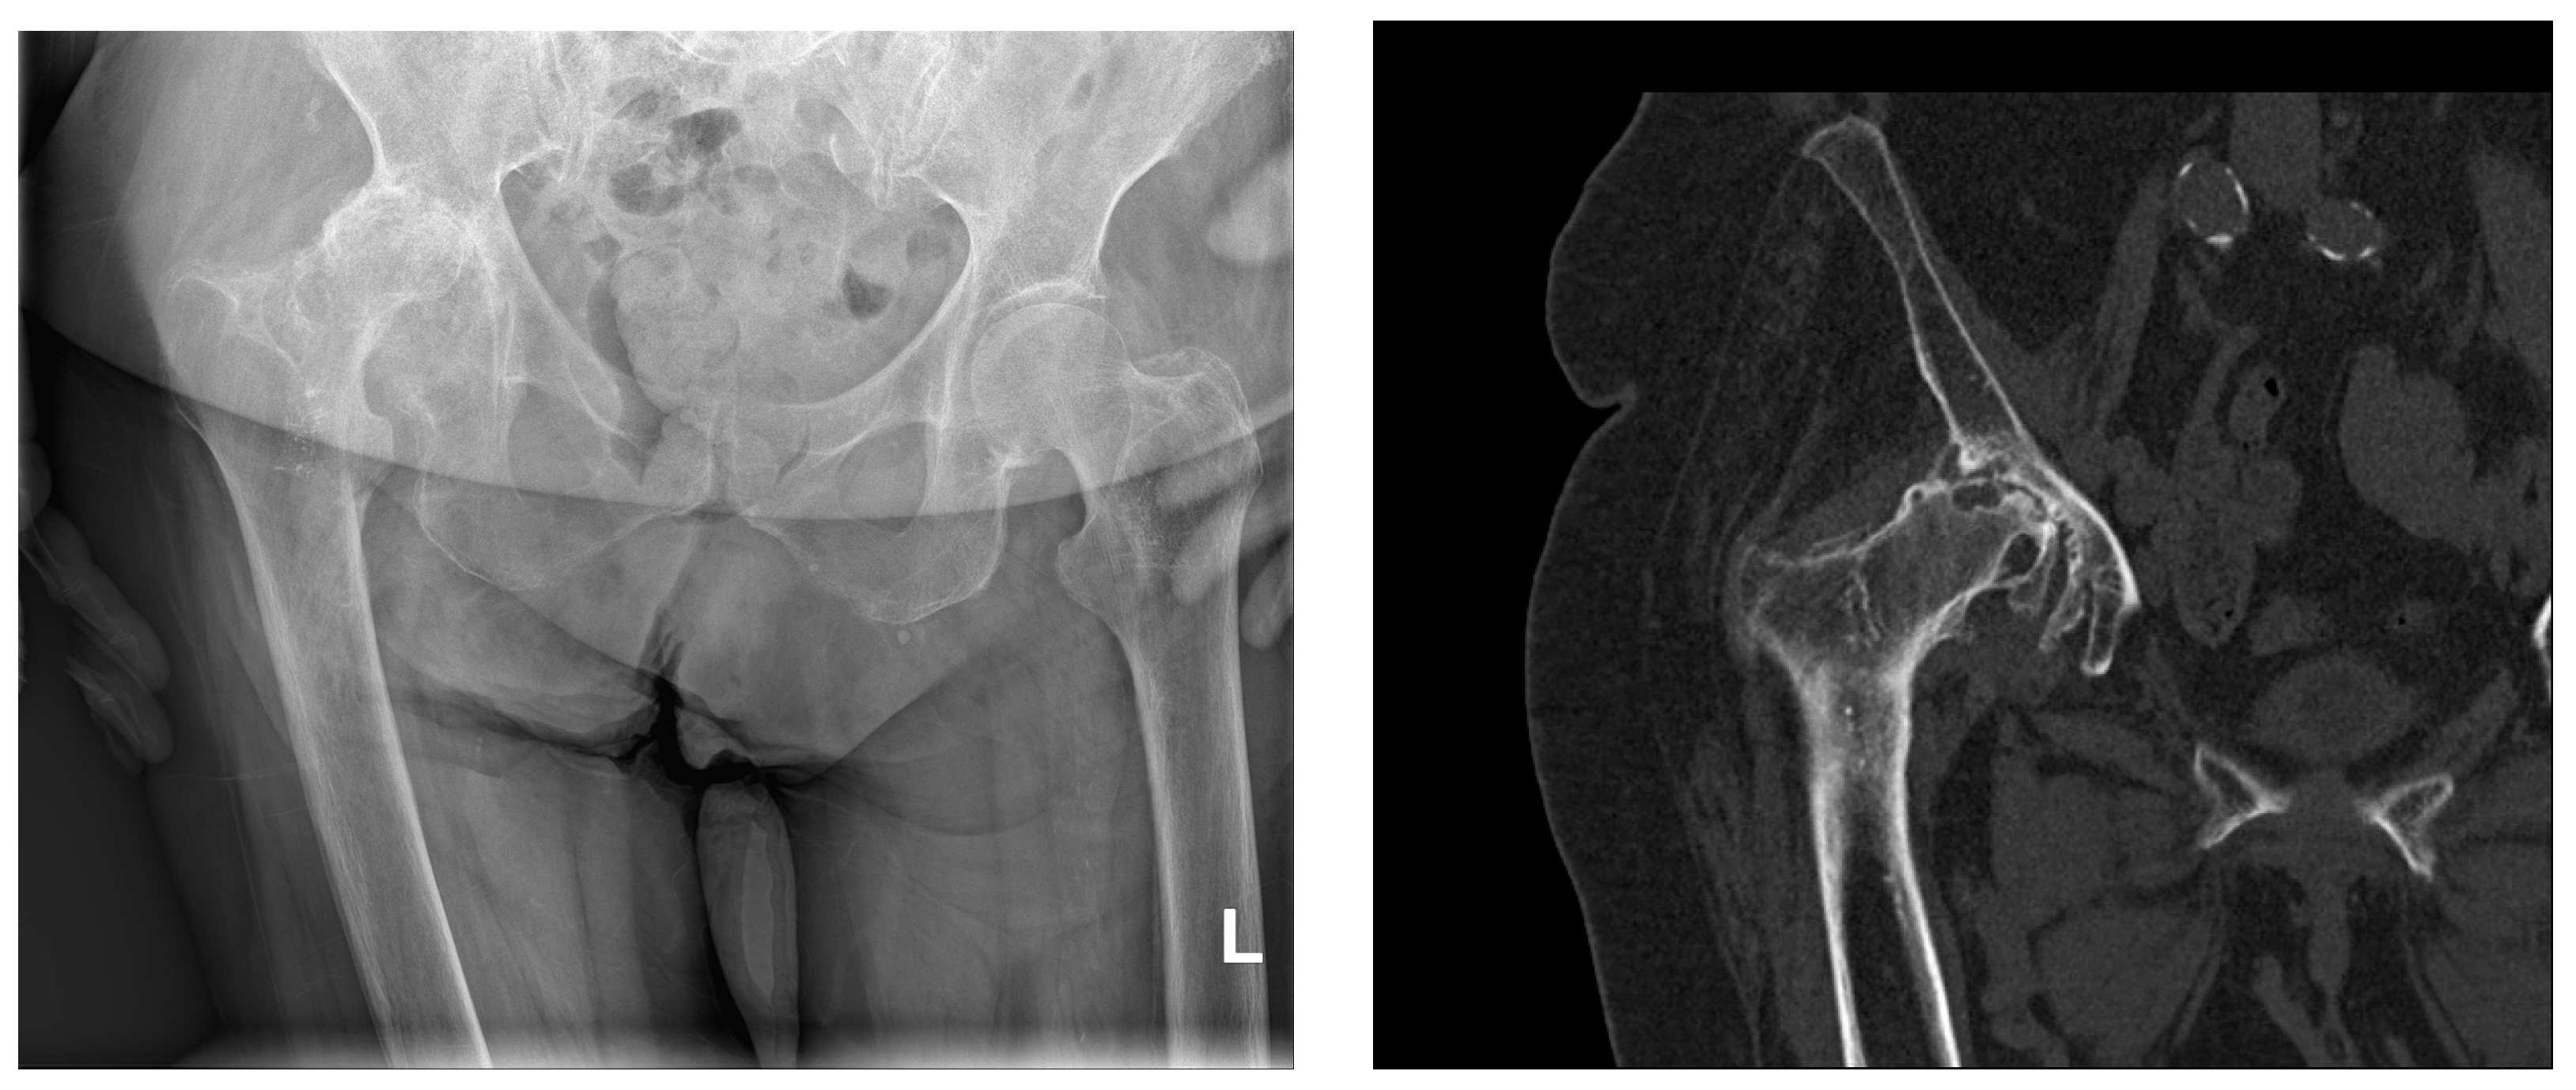

Figure 1. Sagittal X-ray of the pelvis and computerized tomography of the right hip (same patient). Severe right-sided coxarthrosis deformans. Grossly reduced joint space. Dense, sclerotic subchondral bone tissue of the deformed articular bodies interspersed with cyst-like transparencies of bone. Abundant marginal osteophytes of the articular surfaces and femoral head subluxation with consequent higher position of the right half of the pelvis. L—left side.

As degenerative changes progress, the articular cartilage deteriorates, and the joint space decreases, which is evident on X-rays as a narrowing of the joint space. The joint surfaces become deformed, flattened, uneven, or irregularly shaped. The latter is the result of focal cartilage proliferation that calcifies, leading to double or triple contour deformities on X-rays (Figure 1). Subchondral sclerosis of the joint surfaces can progress to eburnation (ivory-like appearance). Convex joint bodies lose their convexity, while concave joint bodies become shallower and flattened. Hypertrophic changes in the form of osteophytes develop chronically along the edges of the joint surfaces. Increasing osteophytes can result in a bony bridging between the articulating joint surfaces. Bone pseudocysts appear as cyst-like, marginally sclerotic transparencies in the subchondral area, varying in size and shape. Enlarged pseudocysts can cause subluxation of the joint bodies and the presence of loose bone fragments, called joint mice, in the joint space. Fracture of the bony wall of a pseudocyst can create communication between the joint cavity and the denuded joint body. Since 1957, the Kellgren and Lawrence classification has been used for the assessment of osteoarthritis changes in radiological practice. The radiological analysis includes osteophytes, periarticular ossifications, changes in articular cartilage associated with subchondral sclerosis of bone tissue, and pseudocysts in the subchondral bone tissue. According to the radiological findings, osteoarthritis changes are graded into five stages (0–4) [54].

Complete joint ankylosis as a result of osteoarthritis is rarely seen today. Cartilaginous elements in some joints often become calcified (chondrocalcinosis which should be differentiated from calcium pyrophosphate dihydrate deposition disease), such as the menisci in the knee joint or the glenoid labrum in the shoulder joint. The radiographic findings often do not correspond to the subjective complaints of the patients, so in the presence of a rich physical examination and clinical picture, the radiographic findings may be only minimally altered. Computed tomography, compared to conventional radiographic imaging of joints affected by osteoarthritis, provides richer data on the extent of the pathoanatomical substrate.